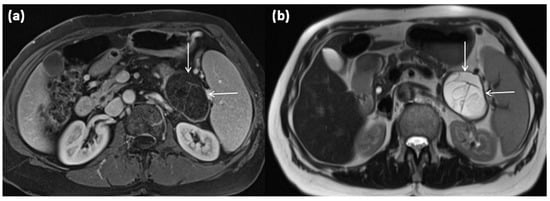

Figure 5.

MRI of a 67-year-old female patient with T1w sequence after gadolinium-based contrast administration (a) and T2w sequence (b). A large multicystic mass of the pancreatic tail (arrows) with tiny septa in T2w, as well as mild contrast enhancement of each septa, is seen.